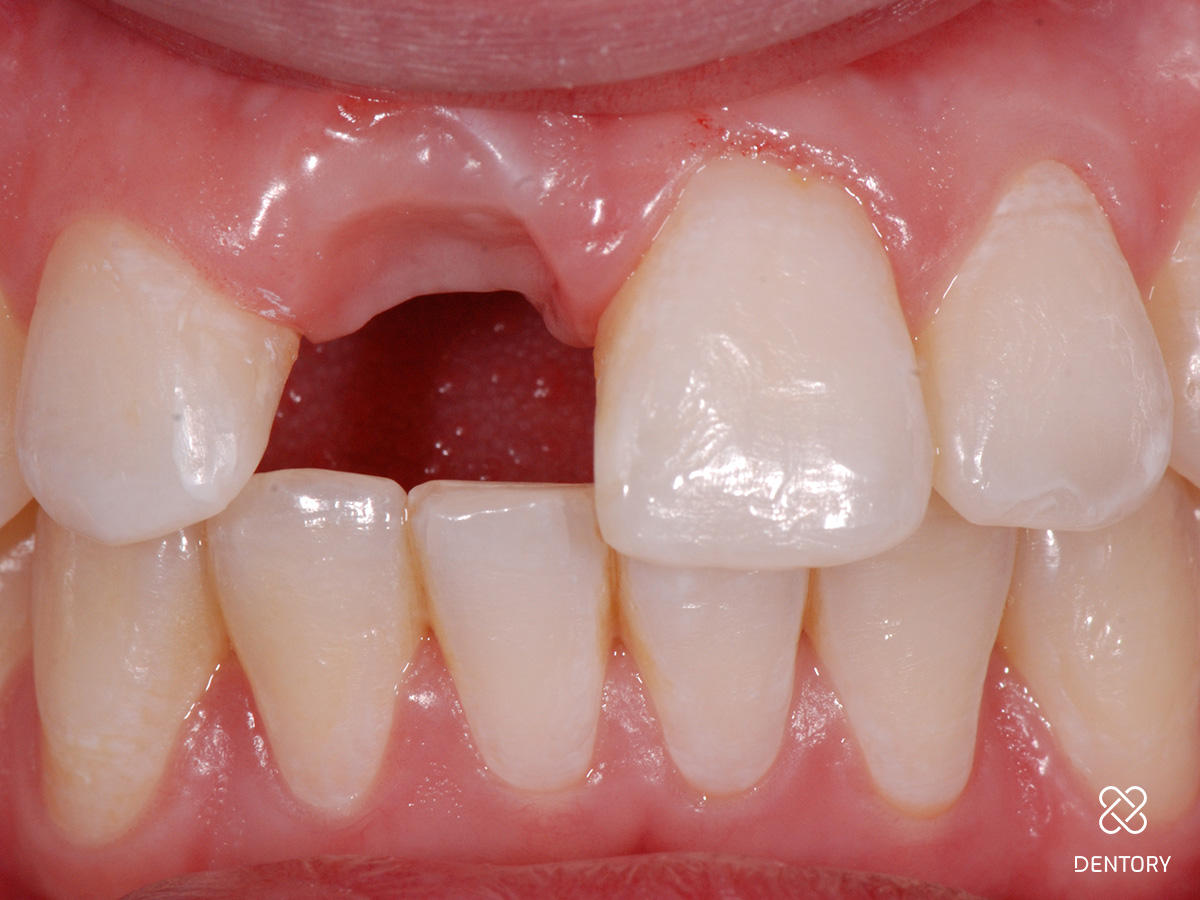

Abbildung 24

Abschlussbild.

Folgebehandlung

Bereits 2 Monate nach Zahnentfernung wurde zur mittelfristigen oder auch längerfristigen Versorgung der Lücke beim Hauszahnarzt eine vollkeramische Klebebrücke adhäsiv befestigt bis ggf. eine Implantatbehandlung gewünscht und möglich ist.

Zusammenfassung

Ein deutlicher Gewinn an Weichgewebshöhe im Vergleich zur Ausgangssituation ist sichtbar; es wurde ein symmetrischer Gingivaverlauf erzielt; die Kammbreite ist durch die Kombination aus Hart- und Weichgewebsaufbau gut erhalten geblieben.